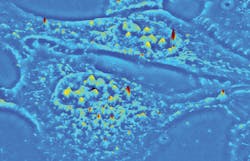

The established QPI technique known as spatial light interference microscopy (SLIM) excels at investigating thin, transparent samples such as single cells (see image above). Now, a new QPI technique called gradient light interference microscopy (GLIM) extends label-free and quantitative 3D tomographic imaging to optically thick, strongly scattering tissues with high resolution and remarkable contrast. Both have important implications for life sciences research and drug discovery.

Real-time, nondestructive SLIM (see Fig. 1) uses optical interferometry to reveal structure and dynamics with nanometer sensitivity in live cell cultures in 4D (3D time-series).51,52,35 In PC illumination, light beams emanating from the condenser ring pass through the sample and are collected in the back focal (Fourier) plane of the microscope objective.53 This scattered beam light is geometrically separated from the reference beam in the Fourier plane, and combined through interference in the image plane.A phase plate in the Fourier plane advances the phase of the reference beam by 0.5π radians and attenuates its amplitude. Destructive interference generates a dark image for the dense portions of the cell with respect to the gray background. The SLIM module includes a one-to-one 4f relay system with a spatial light modulator (SLM) in the Fourier plane, and relays the microscope image plane with minimal aberrations (diffraction-limited) at a 1:1 ratio to a camera placed at its exit port. A phase mask ring, projected on the SLM screen at the same size, is conjugated with the back focal plane of the microscope objective. The SLM thus modulates the reference beam like a phase plate with variable thickness.

To create a quantitative phase image, the SLM shifts the phase of the reference beam by a fixed amount (0, 0.5π, π, 1.5π) and the camera captures the intensity image. A quantitative phase image is uniquely determined by combining the four frames and solving the field interference equations at each pixel. SLIM has successfully measured cell cycle-dependent growth and kinetics,54,55 enabled study of red blood cell structure,56 characterized the 3D structure of unlabeled live cells,57,48 and facilitated development of label-free cancer markers.58,59